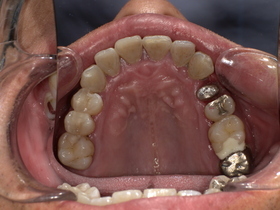

治療前の状態|詰め物の劣化と二次虫歯

診察の結果、以下の問題が確認されました。

■ 二次虫歯(再発虫歯)

詰め物と歯の隙間から細菌が侵入し、

👉 内部で虫歯が進行している状態

■ 適合不良(段差・隙間)

- 汚れが溜まりやすい

- 歯周病リスク増加

■ 噛み合わせの乱れ

欠けた状態を放置していたため、

👉 他の歯に負担がかかっていました

症例結果|Before / After

Before

- 詰め物が脱離

- 清潔感に欠ける状態